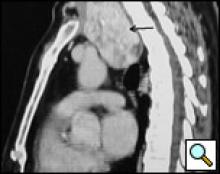

A 58-year-old Chinese man presented with a dry cough of three months’ duration. A chest x-ray at a local hospital revealed "a shadow in the superior mediastinum." A subsequent CT scan suggested "ectopic intrathoracic thyroid" (Figures 1 and 2). His physical examination revealed normal temperature and heart rate, without any signs of hyperthyroidism. Palpation of the neck revealed a non-tender, firm, fixed, and non-pulsatile 2 cm right inferior thyroid mass. A repeat chest x-ray confirmed a mass in the right anteromedial mediastinum, with smooth margins, tracheal compression, and deviation of the trachea to the left (Figure 3). Nuclear Tc99 thyroid scan revealed a cold nodule in the right inferior thyroid gland extending below the sternum (Figure 4). The values of total thyroxin 3 (TT3), total thyroxin 4 (TT4), free thyroxin 3 (FT3), free thyroxin 4 (FT4), and thyroid stimulating hormone (TSH) were all normal. Due to the suspicion of malignancy and to avoid the development of tracheomalacia, surgery was performed to remove the mass.